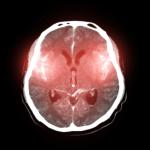

Имунната функция на тялото

Витамин C е важен за поддържането на баланса на oкислително-редукционните процеси в клетките на тялото – това са реакции в клетките, които добавят или премахват кислород и които са ключови за много процеси, включително генерирането на енергия в клетките. Същите тези реакции обаче могат да доведат до образуването на продукти, които са вредни за човешките клетки – например такива, които си взаимодействат с липидите (мазнини), протеините и нуклеиновите киселини. Витамин C може да тушира тези вредни реакции. Освен това помага на ензимите да натрупат колаген, който е необходим за поддържането на клетките на нашите тела.